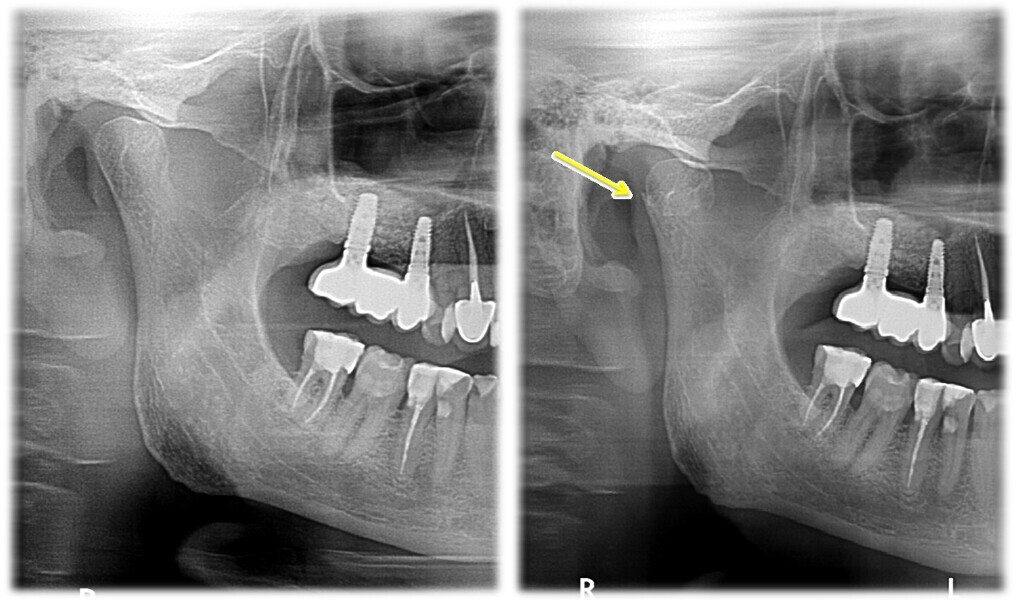

Ryc. 5_Zdjęcia śródoperacyjne – zabieg otwartej repozycji i osteosyntezy złamania głowy żuchwy strony prawej.